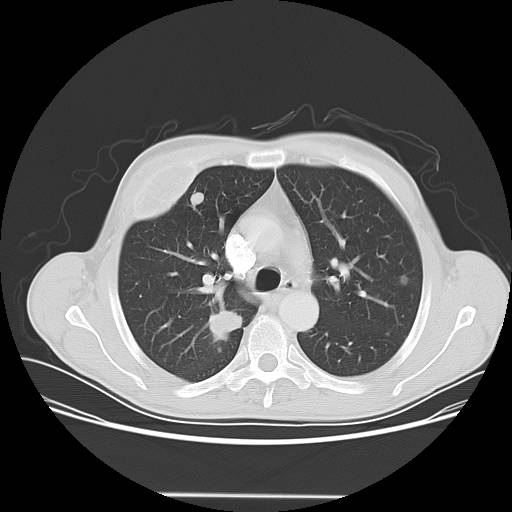

Case 2 CT

IMPRESSION:

1. Likely renal cell carcinoma with multiple metastases to lung, right

3rd rib, and likely right iliac. There is no definite invasion of

adjacent organs or the vasculature.